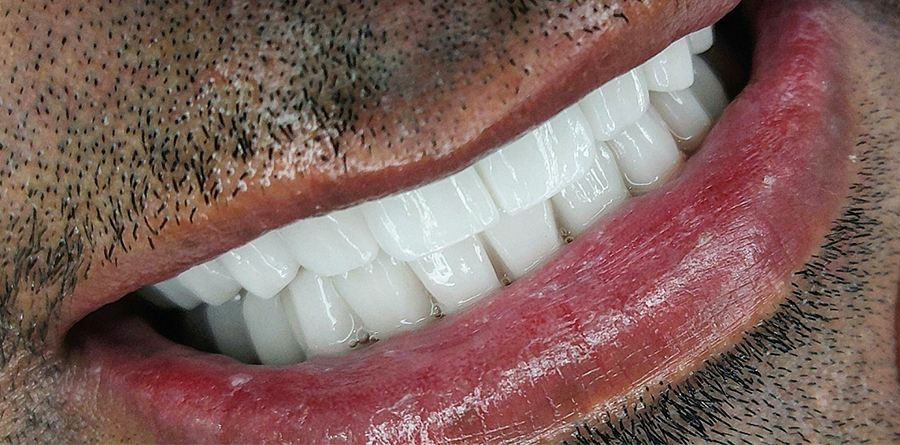

Vorher Nachher